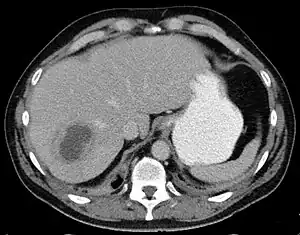

Liver abscess on axial CT image: a hypodense lesion in the liver with peripherally enhancement.